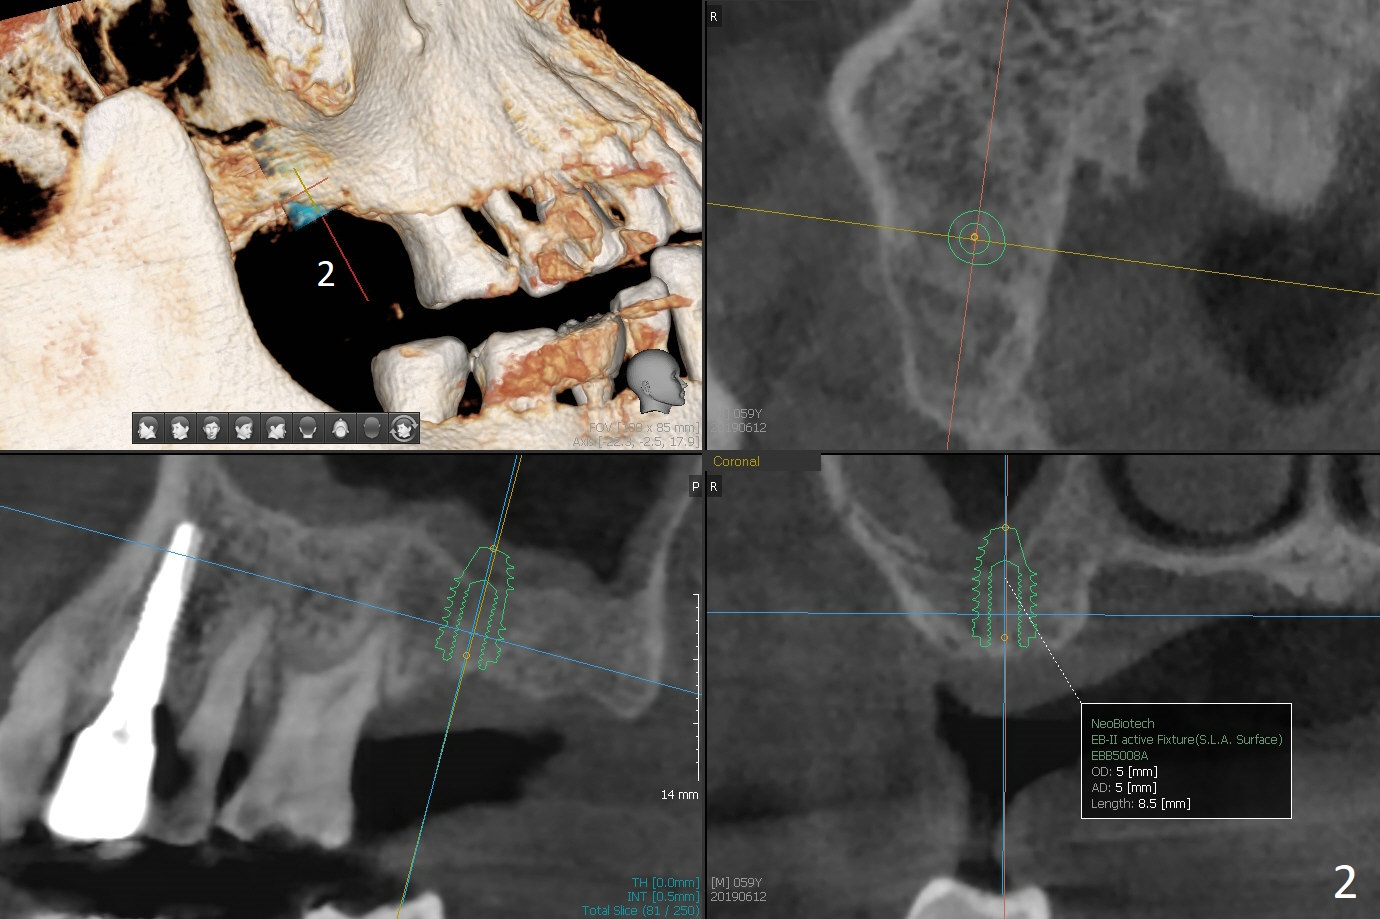

A 59-year-old man requests implant at #2 after those at #5, 14/15, and 29 (Fig.1). Sinus lift is required at #2 (Fig.2). Prepare PRF and SM implant (to be consistent with the previous ones without screw loosening). Although there is periapical radiolucency at #13 (Fig.3 >), there is another between #12 and 13 (Fig.3 *), which may be related to the apical infection at #12 (Fig.4 <).